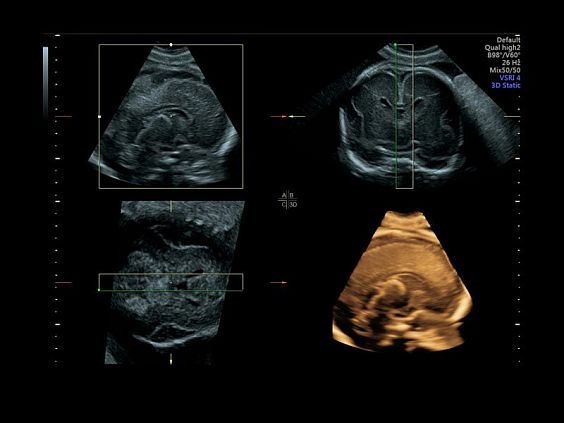

Клинические изображения

Объемное сканирование Voluson — 3D/4D вашей мечты

Объемное УЗИ на Voluson E10 — это не просто потрясающе красивая картинка, это ценный инструмент получения дополнительной информации при обследовании женщин.

Voluson E10 поддерживает инновационные технологии формирования изображений — HDlive Silhouette и HDlive Flow, которые позволяют увидеть мельчайшие детали. Алгоритм SonoRenderlive упрощает рабочий процесс и дает возможность реконструировать изображение поверхностей, определяя область перехода между тканью и жидкостью.

• SonoRenderlive

• Улучшает объемную визуализацию за счет автоматического определения линии начала реконструкции при изображении поверхностей. При исследовании в режиме 4D функция SonoRenderlive непрерывно обновляет положение исходной линии с учетом движений плода.

• Технология HDlive Silhouette — задает разный уровень прозрачности, помогая выявлять контуры внутренних структур и точнее оценивать состояние плода в первом триместре.

• Технология HDlive Flow — повышает реалистичность визуализации сосудистых структур, улучшая восприятие глубины (по сравнению с традиционным цветовым допплером и функцией HD-Flow).